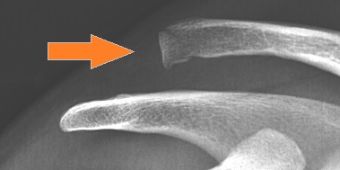

schultereckgelenksprengung

Schultereckgelenkssprengung mit hochstehendem Schlüsselbein (Pfeil).

Diagnostik: oft als Blickdiagnose bereits sichtbar

Die Fehlstellung der Gelenkpartner ist dabei oft schon durch die veränderten Hautkonturen sichtbar, da sich das Schlüsselbeinende nach oben bewegt (Bild). Die weitere Abklärung erfolgt durch Röntgenaufnahmen in 3 Ebenen sowie Aufnahmen unter Zugbelastung im Seitenvergleich, um das Ausmaß der Instabilität festzustellen.